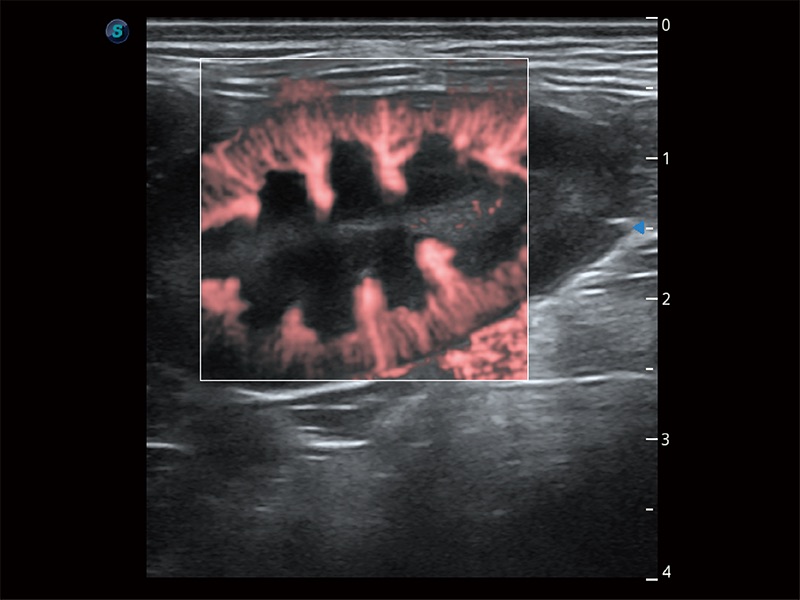

(犬)肾脏显微血流